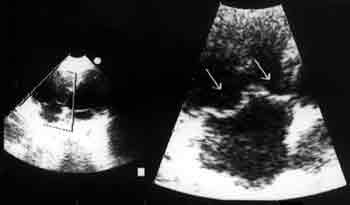

Рисунок. Сонограмма ребенка с ПТК в апикальной четырехкамерной позиции. Режим увеличения ZOOM. Стрелками отмечены передняя и септальная створки ТК. В большей степени (на 4 мм.) пролабирует передняя створка (левая стрелка).